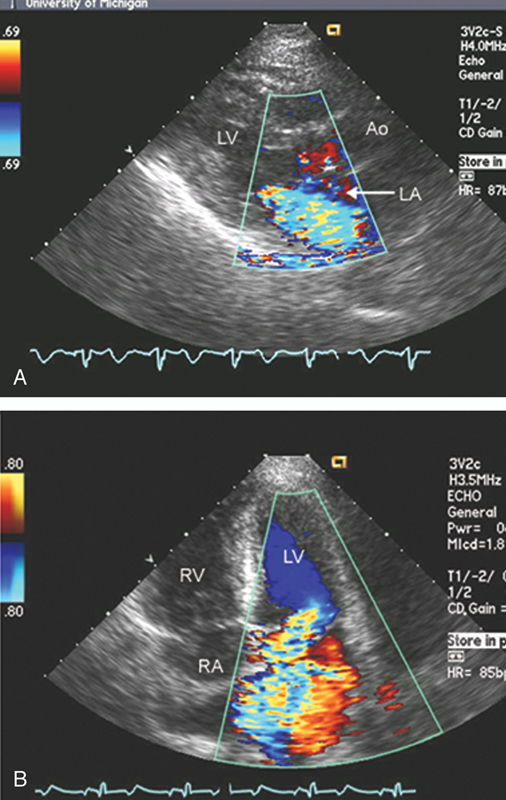

فحوصات تشخيصية لبعض امراض القلب والشرايين التاجية